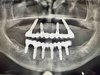

· Проведение хирургических вмешательств с фокусом на полную реабилитацию (All-on-4/6) с немедленной нагрузкой.

· Выполнение сложных костно-пластических операций, включая латеральный синус-лифтинг с одномоментной имплантацией.

· Комплексная имплантация: All-on-4, All-on-6 (FP-1), одномоментная и отсроченная имплантация.

· Костная пластика: латеральный и крестальный синус-лифтинг, направленная костная регенерация (НКР), аугментация альвеолярного гребня.

· Работа с системами: Nobel Biocare, Straumann, Ankylos (Dentsply Sirona), Astra Tech, Osstem, Dentium, Bicon, AWI.